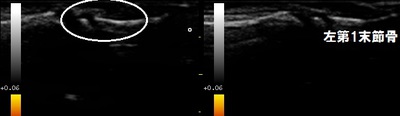

右・左親指 末節骨 超音波長軸像

川越市 6歳の女の子 車のドアに挟んじゃった!! 右手親指の痛み。

昨日、誤って車のドアに右手の親指を挟んでしまいました。1時間ほど痛くて泣いていました。翌日、右の

親指は爪の周囲が内出血で腫れていました。指の曲げ伸ばしは少し痛むけど可能でした。

念のため超音波検査を行いましたが、骨折は認められませんでした。「よかった~」付添いのお母さんンが